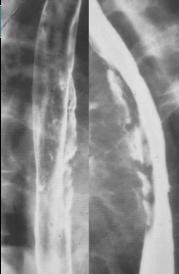

Nombreux de

grande ulcere avec image de extravation de contrast

baryte a exterieure et en longitudinale de oesophage

. . Image TOGD de oesophage . |

Image de

oesophagite a CMV situe 1/3 inferieure de oesophage

avex image des ulceres profondes de oesophage (

fleche blanche ) |